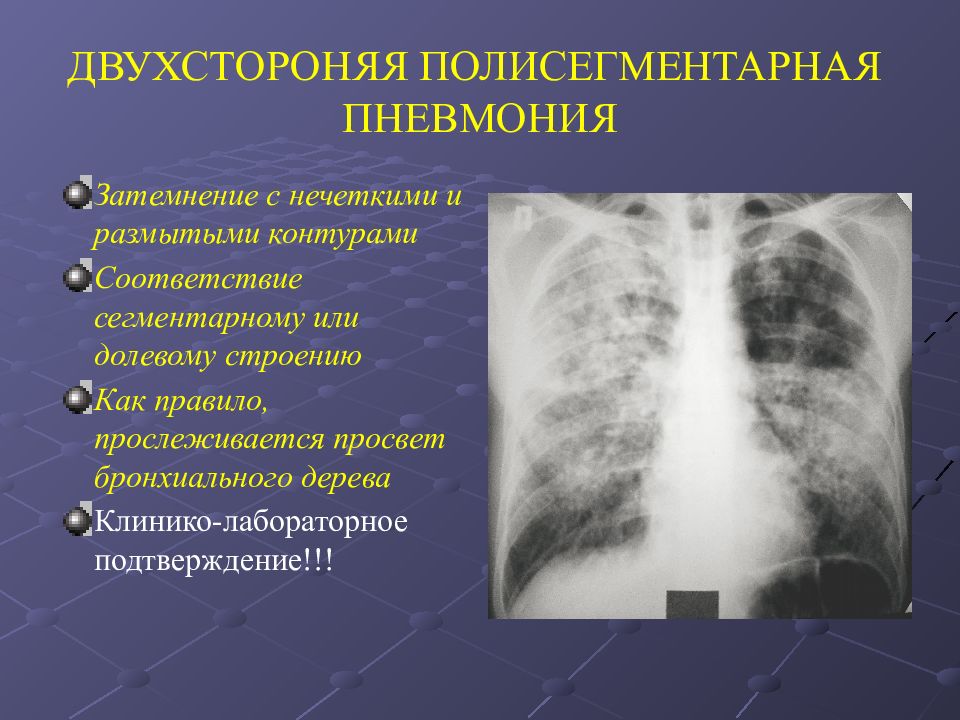

Рентгенодиагностика бронхопневмонии: Советы и примеры